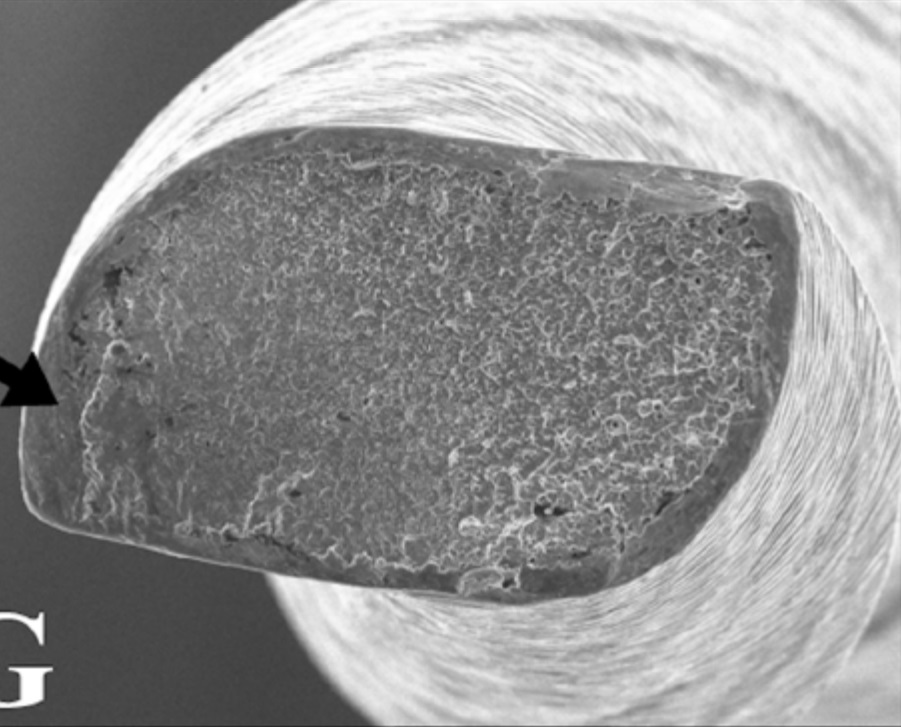

Имеют S-образное сечение[2].